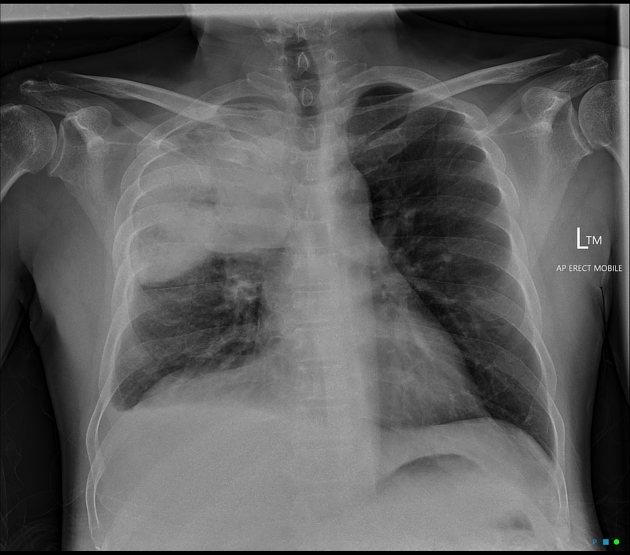

CLINICAL HISTORY:

32yo Female

Dyspnoea

FINDINGS:

Bilateral reticulonodular shadowing with diffuse cystic changes.

Lung volumes are preserved.

No pleural abnormalities demonstrated.

Heart size is normal.

Hila and mediastinal contours are normal.

IMPRESSION:

Lymphangioleiomyomatosis

DIFFERENTIAL DIAGNOSIS:

Langerhans Cell Histiocytosis (Usually has a smoking history and present in an older age group)

Overlapping emphysematous and granulomatous disease